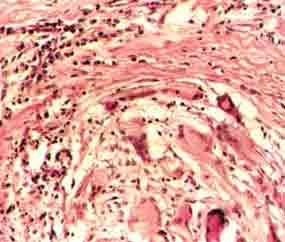

組織病理:

1.典型異物反應為巨噬細胞及異物巨細胞包圍異物,細胞質內可見有吞噬的異物,尚可見異物如縫線、液狀石蠟油、矽鹽毛髮等均可引起異物反應。

2.異物過敏反應,可出現上皮樣細胞構成的結核樣結節,具有巨細胞及乾酪樣壞死,但缺乏或少有吞噬異物現象鈷鈹或紋身顏料可引起異物過敏反應。

3.一些特異性異物肉芽腫,如紋身肉芽腫可見顏料顆粒矽肉芽腫為非結核性肉芽腫為多數巨噬細胞和多核細胞的炎症浸潤,可見折光性強的針狀矽結晶。